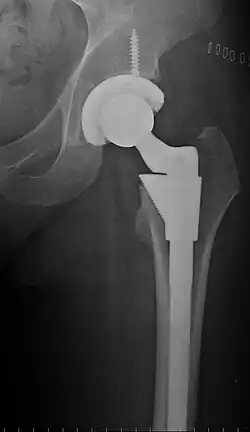

Post-operative projectional radiography is routinely performed to ensure proper configuration of hip prostheses.

The direction of the acetabular cup influences the range of motion of the leg, and also affects the risk of dislocation.[16] For this purpose, the acetabular inclination and the acetabular anteversion are measurements of cup angulation in the coronal plane and the sagittal plane, respectively.

![Acetabular inclination.[95] This parameter is calculated on an anteroposterior radiograph as the angle between a line through the lateral and medial margins of the acetabular cup and the transischial line which is tangential to the inferior margins of the ischium bones.[95]](./_assets_/Acetabular_inclination_of_hip_prosthesis.jpg)

![Acetabular inclination is normally between 30 and 50°.[95] A larger angle increases the risk of dislocation.[16]](./_assets_/Range_of_acetabular_inclination.png)

Acetabular anteversion.[96] This parameter is calculated on a lateral radiograph as the angle between the transverse plane and a line going through the (anterior and posterior) margins of the acetabular cup.[96] -

Acetabular anteversion is normally between 5 and 25°.[16] An anteversion below or above this range increases the risk of dislocation.[16] There is an intra-individual variability in this method because the pelvis may be tilted in various degrees in relation to the transverse plane.[16] -

![Leg length discrepancy after hip replacement is calculated as the vertical distance between the middle of the minor trochanters, using the acetabular tear drops[95] or the transischial line[16] as references for the horizontal plane. A discrepancy of up to 1 cm is generally tolerated.[95][16]](./_assets_/Leg_length_discrepancy_after_hip_replacement.jpg)

Center of rotation: The horizontal center of rotation is calculated as the distance between the acetabular teardrop and the center of the head (or caput) of the prosthesis and/or the native femoral head on the contralateral side.[95] The vertical center of rotation instead uses the transischial line for reference.[95] The parameter should be equal on both sides.[95]